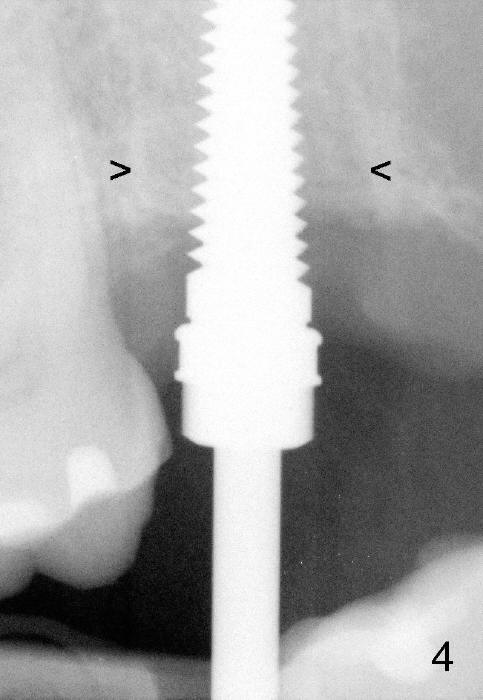

A 57-year-old lady presents for abscess buccal to the tooth #15 (Fig.1 A). Mesial and distal to the occlusal composite (Fig.2 C) is a crack line. In addition to long furcated roots, the upper border of the bone is not shown in this preop PA (arrow). Fig.3 is taken to show a thin septum surrounded by the mesiobuccal (MB), distobuccal (DB) and palatal (P) sockets (Fig.3). Osteotomy is initiated in the septum by 1.2 and 1.5 mm pilot drills, followed by 2,3,4 mm rounded tapered osteotomy at the depth of 17 mm. Nose blowing test is carried out after each step with negative result. Stability is achieved when a 4.5 mm tap is inserted at 17 mm, but the upper end of the tap is not visible (Fig.4,5). When a 5 mm tap is placed, stability is decreased, probably because the coronal end of the septum starts to break down (due to expansion). To re-gain stability, the 5 mm tap needs to go deeper. A 6 mm tap also achieves satisfactory stability at 20 mm. When the tap is removed, there is no air leakage. A 6x20 mm implant is placed with insertion torque > 60 Ncm; the upper end of the implant is still out of view in PA (Fig.6). Another problem is that the implant needs to go deeper to obtain sufficient occlusal clearance. The lower first molars and the 2nd premolars are missing. A panoramic X-ray has to be taken to show the apical end of the implant: ~ 3 mm into the sinus (Fig.7 ^). The maxillary tuberosity appears to grow downward (arrow). In other word, the tooth #15 appears to have been intruded due to overloading.